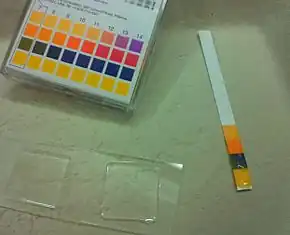

- Loss of acidity. To control bacterial growth, the vagina is normally slightly acidic with a pH of 3.8–4.2. A swab of the discharge is put onto litmus paper to check its acidity. A pH greater than 4.5 is considered alkaline and is suggestive of bacterial vaginosis.

In clinical practice BV can be diagnosed using the Amsel criteria:[30]

- pH of vaginal fluid >4.5

- Release of a fishy odor on adding alkali—10% potassium hydroxide (KOH) solution.

At least three of the four criteria should be present for a confirmed diagnosis.[34] A modification of the Amsel criteria accepts the presence of two instead of three factors and is considered equally diagnostic.